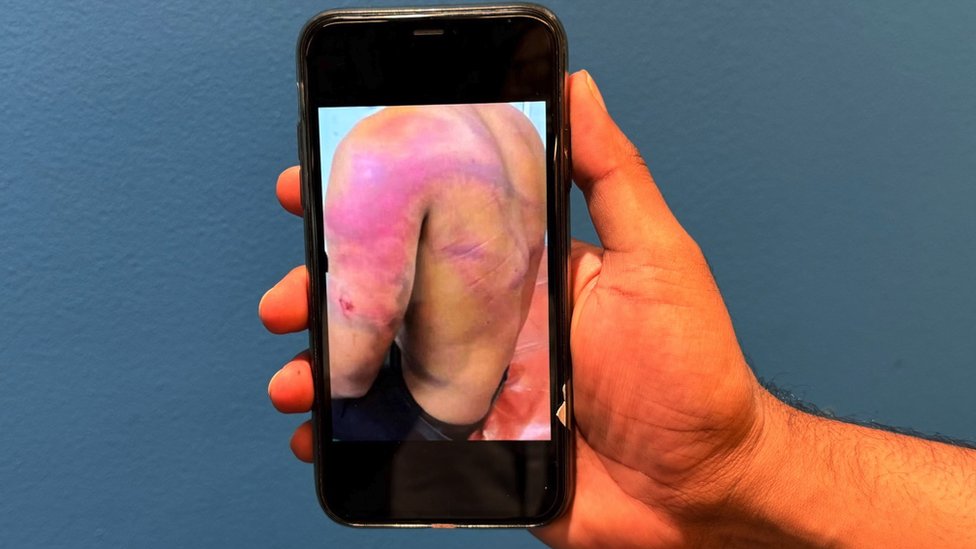

Kad sam se osvetila, moj ginekolog mi je rekao da nema znakova endometrioze, ali da imam zakrčene vene.

Moj poslednji pregled na transvaginanlnom ultrazvuku prvi put je ciljano tražio „zakrčenje u karlici“ i moj ginekolog se sad prvi put uverio u dokaze za to, ali nije bio uveren da te vene mogu da izazovu nivo bola koji doživljavam.

On je potvrdio da imam pelvički kongestivni sindrom u levim i desnim venama jajnika i u delovima druge vene u mojoj karlici, bočnoj veni.

Emobilizacija koju sam imala 2. avgusta 2018. godine blokirala je moje zakrčene vene metalnim kalemima da ne mogu više da se pune krvlju, uvećavaju i nanose mi bol.

Od tada su se moji simptomi značajno poboljšali, ali i dalje umem da imam gadne menstrualne bolove.